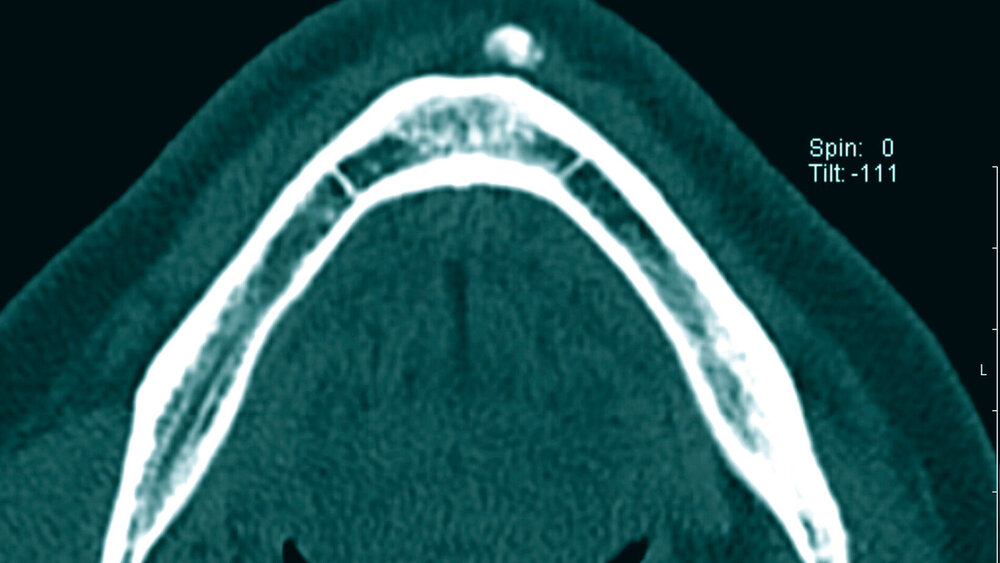

Die CT-Untersuchung zeigte ein knochendichtes Substrat in einer Ausdehnung von 1 cm Länge, 0,7 cm Höhe und etwa 3 mm Breite in den Kinnweichteilen paramedian links ohne direkten Kontakt zum Unterkieferknochen sowie außerhalb der Kinnweichteilmuskulatur. Das mitgebrachte Orthopantomogramm war bei Überlagerungseffekt unauffällig. Bei bestehender Wachstumstendenz und zur diagnostischen Abklärung wurde mit dem Patienten die operative Entfernung des Substrats vereinbart.